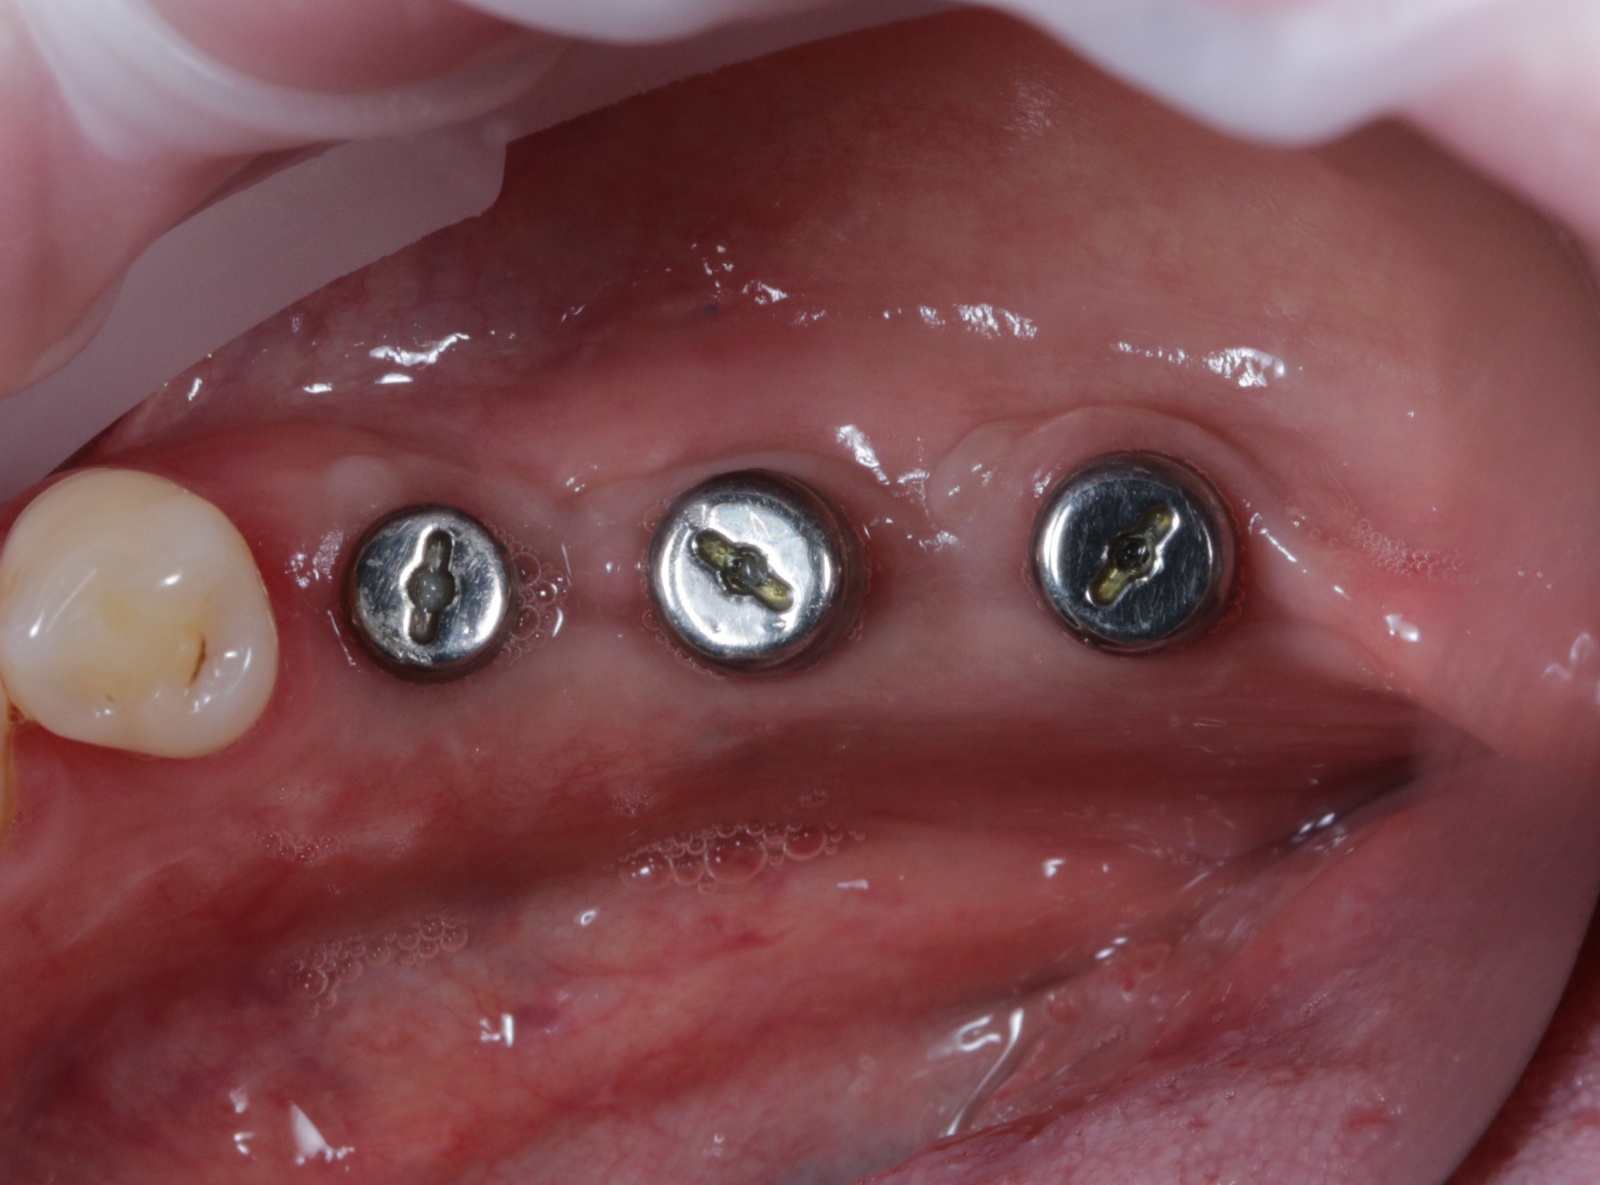

Была произведена антисептическая обработка и установка формирователей десны. Фото ниже сделано на момент восстановления.

Как можно заметить, костная ткань не так сильно «пострадала», как в предыдущем случае (недокрученный формирователь десны на снимке слева был докручен).

Изготовлены временные коронки из фрезерованной пластмассы на 3х имплантатах уже с винтовой фиксацией (снимок с зеркалом, это не другая сторона).